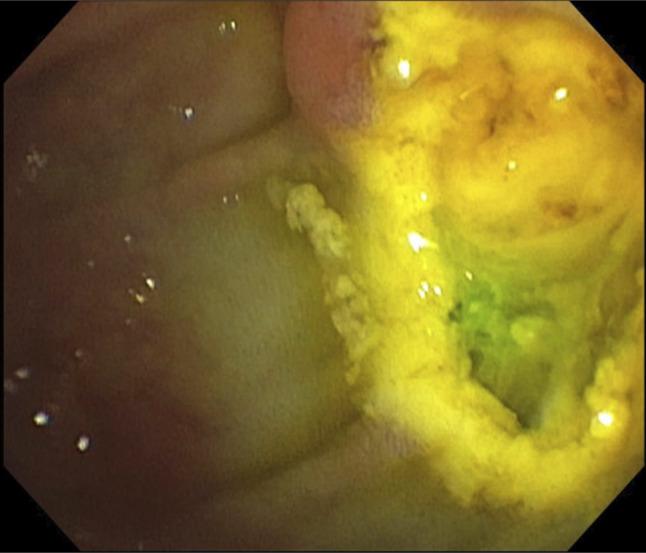

胆道射频消融是一种新兴的辅助和姑息性治疗壶腹和胆道肿瘤的患者。鉴于这些恶性肿瘤的高死亡率,有关长期并发症的数据有限。我们报告一个独特的病例括约肌切开术再狭窄导致胆道梗阻,在一个98岁的妇女壶腹腺癌的历史,治疗乳头切除和胆道射频消融(RFA)。内镜逆行胆管造影显示括约肌切开术部位再狭窄,通过重复括约肌切开术和支架置入术成功处理。本病例强调括约肌切开术再狭窄是胆道RFA的潜在晚期并发症,并强调RFA后患者需要意识到延迟性胆道梗阻。

Biliary radiofrequency ablation is an emerging adjunctive and palliative therapy for patients with ampullary and biliary tumors. Given the high mortality for these malignancies, data on long-term complications are limited. We report a unique case of sphincterotomy restenosis causing biliary obstruction in a 98-year-old woman with a history of ampullary adenocarcinoma treated with papillectomy and biliary radiofrequency ablation (RFA). Endoscopic retrograde cholangiopancreatography revealed restenosis at the sphincterotomy site, managed successfully with repeat sphincterotomy and stenting. This case highlights sphincterotomy restenosis as a potential late complication of biliary RFA and emphasizes the need for awareness of delayed biliary obstruction in post-RFA patients.